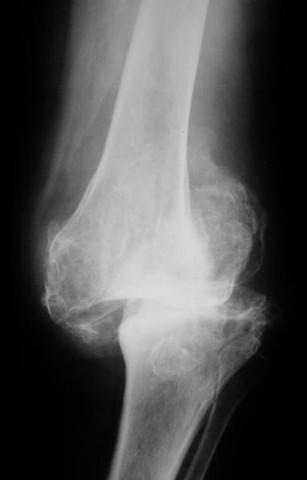

ПКК, СУЕ, кръвна глюкоза и HbA1С (за оценка на гликемичния контрол при диабетици), нива на алкална фосфатаза, калций, фосфор, паратиреоиден хормон, креатинин, серумно ниво на витамин В12, чернодробни ензими, рентгенография, КАТ, ЯМР, ултразвукова доплерова сонография, лумбална пункция (при показания), синовиална и костна биопсия (при необходимост), инфрачервена термография, течнокристална термография или термисторна термометрия и други.

- Инструментални изследвания: